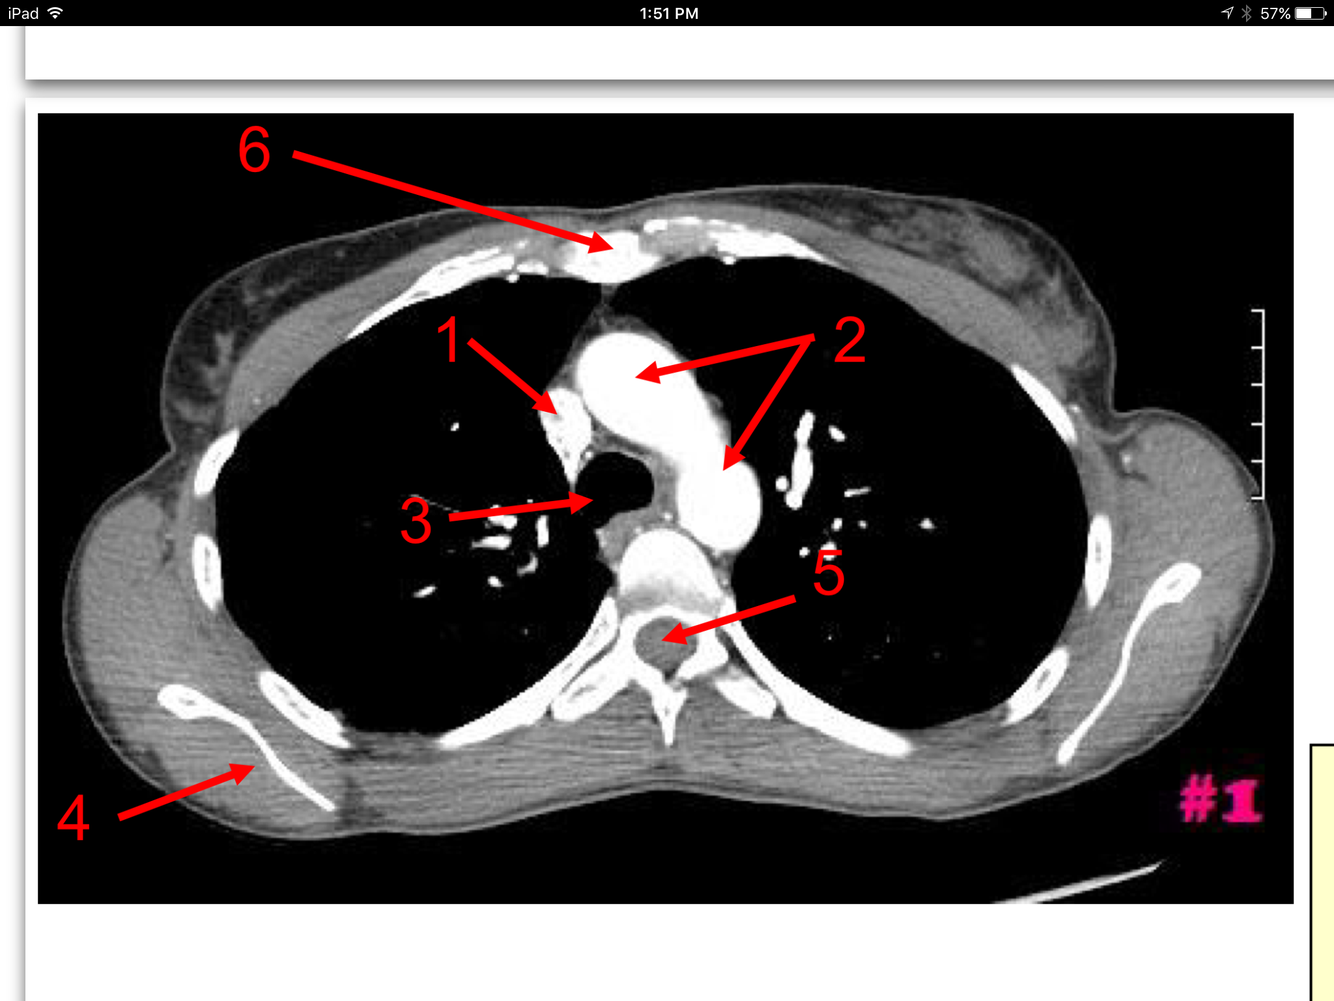

1

Superior Vena Cava

Arch of the Aorta

Trachea

Body of the Rt scapula

Spinal cord

Body of the sternum